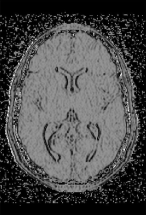

Note that, given an edge , the Ricci curvature represents in a way a generalized mean of the weights the cells parallel to . Therefore, it represents a measure of flow in the direction transversal to . It follows, that, contrary perhaps to intuition, this type of Ricci curvature (and the Bochner Laplacian associated to it) in direction, say, parallel to the -axis, is suitable for the detection of edges and ridges in the -direction. On the other hand, since scalar (i.e. Gauss) curvature, is associated to each pixel, that is to each square of the tessellation, to compute the Gaussian curvature one has to compute the arithmetic mean of the Ricci curvatures of edges of the square under consideration – see Fig. 2. (A similar argument holds if one wishes to compute the 1-Laplacians, and , of a given pixel.) The difference between the Ricci curvature computed in the horizontal and vertical directions, as well the “true”, i.e. average Ricci curvature can be seen in Fig. 3 and Fig. 4.

As Fig. 5 illustrates, the Combinatorial Ricci curvature we introduced herein allows even for a non-optimal choice of weights, a very good approximation of Gaussian curvature of surfaces (i.e. for gray-scale images). Here, classical Gaussian curvature was computed using finite element methods standard in Image Processing – see [16].

In contrast, both the Bochner (and Riemann) Laplacian sharply diverge from the classical one, e.g. the one obtained by using the standard Matlab function (see Fig. 6). This is not too surprising, given the fact that such a comparison is, in a sense, not relevant, due to the different dimensionality of the two concepts: The Combinatorial and Bochner Laplacian are, as stressed above, associated to edges, hence -dimensional (this being underlined by the notation: and , respectively). In contrast, the classical Laplacian is a pointwise function, (and, in its discrete setting, associated to the vertices of a mesh) hence -dimensional. However, the Bochner Laplacian proves to be an excellent detector of “sharp” edges (see Fig. 7), therefore it may prove to be useful for contour detection and for segmentation.